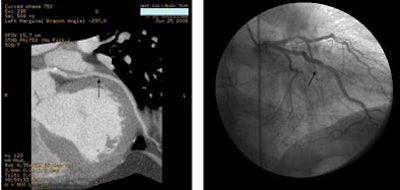

![]() |

| A 59-year-old man presented with classic chest pain symptoms to the ER five days earlier. He was asymptomatic upon presentation to the practice, but opted for an office-based CTA rather than wait three weeks to see a cardiologist. Images top to bottom: Right coronary artery stenosis (arrows) shown on 64-slice CTA at left, cardiac catheterization at right. Next, a normal left circumflex artery (arrows) is depicted on 64-slice CTA at left, cardiac catheterization at right. Next two image sets: Left anterior descending artery stenosis (arrows) is seen on 64-slice CTA at left, cardiac catheterization at right. Bottom image shows excellent outcome on cardiac cath following stenting. |